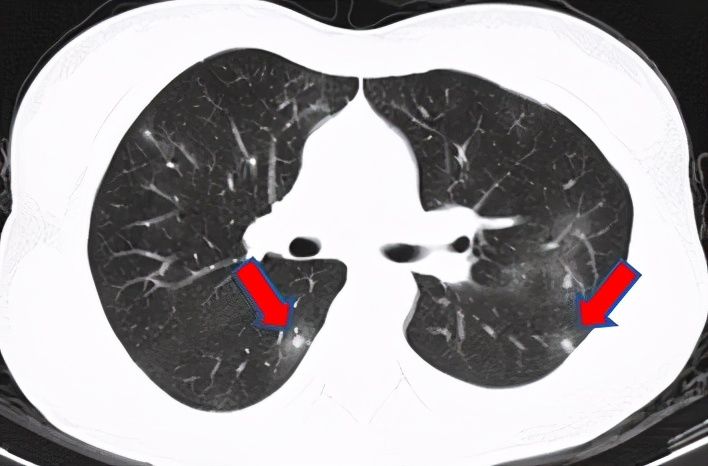

肺吸虫家住江苏的王小姐是个上班族,但平淡的生活却被一阵阵剧烈的咳嗽打断了。干咳到胸痛的王小姐感觉一分钟也忍不了了,半夜去急诊拍了胸部CT,医生看到双肺多发结节影,说不能除外肺癌。王小姐吓得心都提到了嗓子眼,赶紧到感染病科门诊看病。